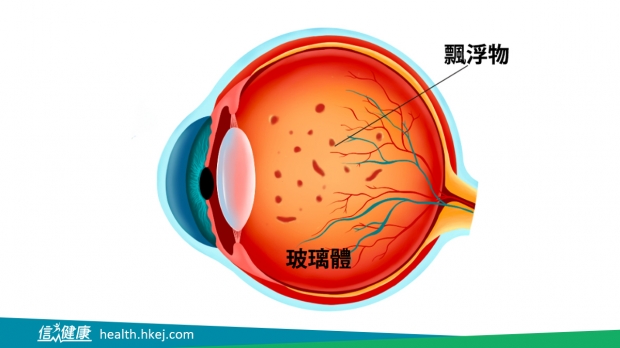

视网膜是眼内一层薄膜,是形成影像的关键,其中包含感光细胞层和视网膜色素上皮层。视网膜脱落是指感光细胞层与视网膜色素上皮层分离,导致感光细胞失去养分及血液的供应而丧失视觉功能。这种情况可以突然发生,没有任何警告,并导致视力丧失。

要重点解说: 飞蚊症不是病,是一种症状,可分急性和慢性。急性飞蚊多数因视网膜裂孔、出血或发炎所引致的飞蚊病征,必须找出病因,及早处理,以减少视力的丧失;慢性或良性飞蚊是因玻璃体分离时,玻璃体胶原质纤维退化产生了杂质,变得混浊,产生了飞蚊征状,对视力影响甚微。